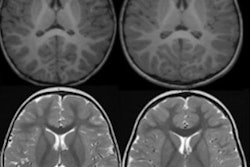

MRI shows that so-called "superagers" -- people in their 80s who have the memory function of much younger individuals -- have more gray matter in brain regions linked to memory function than their peers, a new study in Lancet Healthy Longevity reports.

MRI showed that superagers had more gray matter -- tissue key to brain function -- in areas controlling memory and movement and that this gray matter tissue broke down more slowly over five years compared to the gray matter of typical older adults.